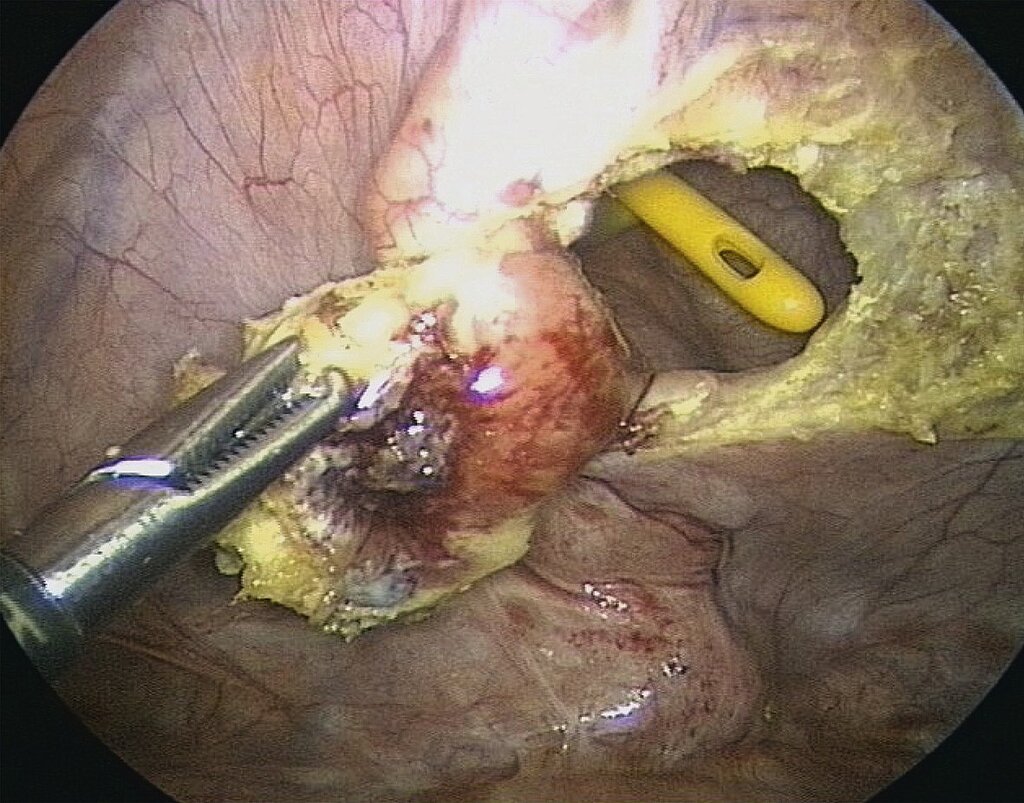

Ovarielle Endometriose

Insbesondere bei Patientinnen mit Kinderwunsch ist große Vorsicht bei der operativen Therapie der Endometriome geboten, da mit jedem operativen Eingriff eine Verringerung der ovariellen Reserve verbunden ist. Dies trifft insbesondere auf die Entfernung des Zystenbalges zu, da hierbei gleichzeitig gesundes Ovargewebe mitentfernt wird; Entscheidungskriterien sind in Tab. 2 aufgeführt. Deutlich schonender verlaufen die Punktion der Zyste mit anschließender Alkoholinstillation bzw. die Eröffnung der Zyste mit anschließender Plasmakoagulation des Zystenbalges. Eine präoperative Aufklärung der Patientinnen über die Möglichkeiten und Kosten des Medical (Social) Freezings ist hilfreich.